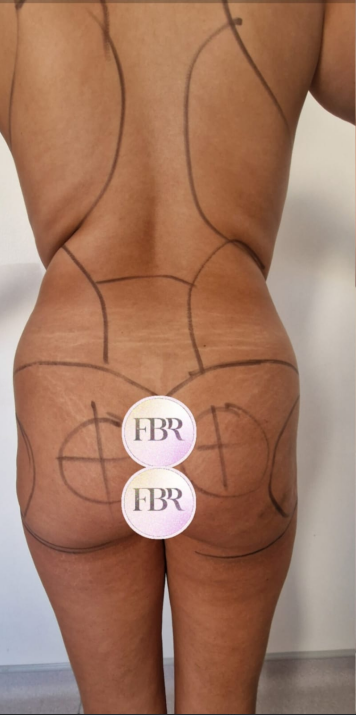

Découvrez les résultats de du lipofilling des fesses sur nos patients

AVANT

APRÈS

Autres résultats

Ces cartes sont cliquables : cliquez ou appuyez sur une carte pour ouvrir le cas en grand (même présentation AVANT / APRÈS que ci-dessus).